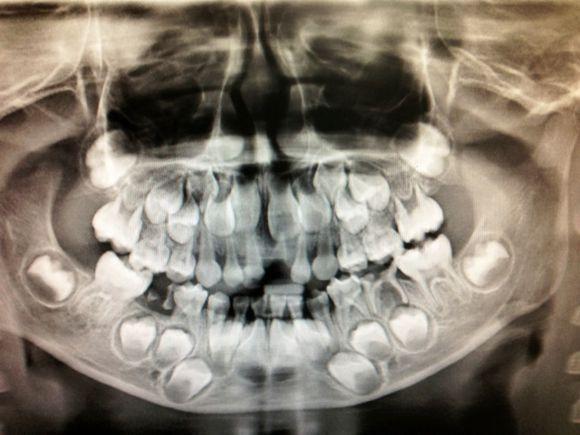

孩子在6-7岁的时候,乳牙换成恒牙,换牙后就伴随着一生,很多父母会奇怪,宝宝的牙齿是怎么生长出来的呢?其实在乳牙还未脱落时,恒牙胚就已经在慢慢发育长大,那么此时的宝宝牙齿是什么样的呢?现在发出几张换牙时的照片,这样会有更直接的了解。

可以看出还未长出的恒牙胚,正在逐渐发育,慢慢向外生长。